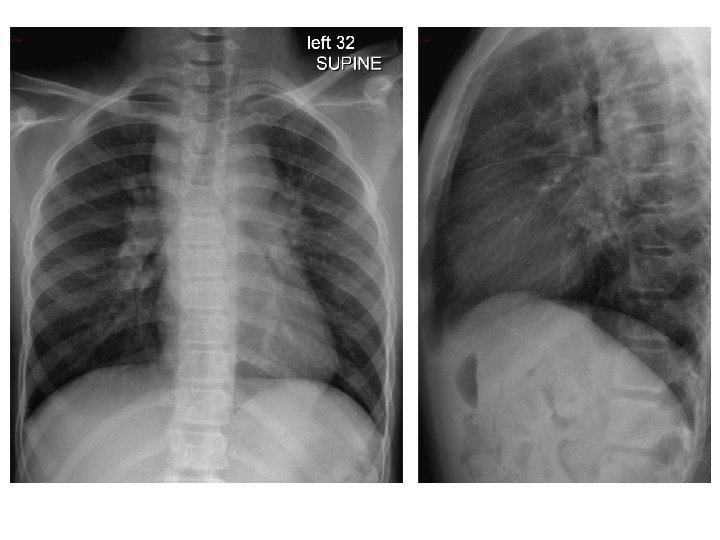

DC, 12 y. o. F • Presented to the ED via EMS with left shoulder, thigh, and rib pain after she rode her bicycle into a concrete wall w/o a helmet • ? LOC, mild HA, no emesis, was moving all extremities after landing in the grass per parents • PMH: seasonal allergies, constipation • PE: significant only for mild abrasions and ecchymosis over left lateral thigh • In ED: FAST, CT head, XR elbow/knee/radius/ulna/shoulder/femur, CXR, CTA chest

Diagnosis/Follow up Diagnosis: Mediastinal& hilar lymphadenopathy/mass Follow up • 1 st clinic visit: Imaging concerning for possible lymphoma, although no worrisome sx, history, labs, or exam findings • PET: “FDG avid mediastinal and hilar lymphadenopathy” • 2 nd clinic visit: fatigue, submandibular adenopathy • CT-guided FNA: “Atypical lymphocytes” – Flow Cytometry: “normal thymic tissue”